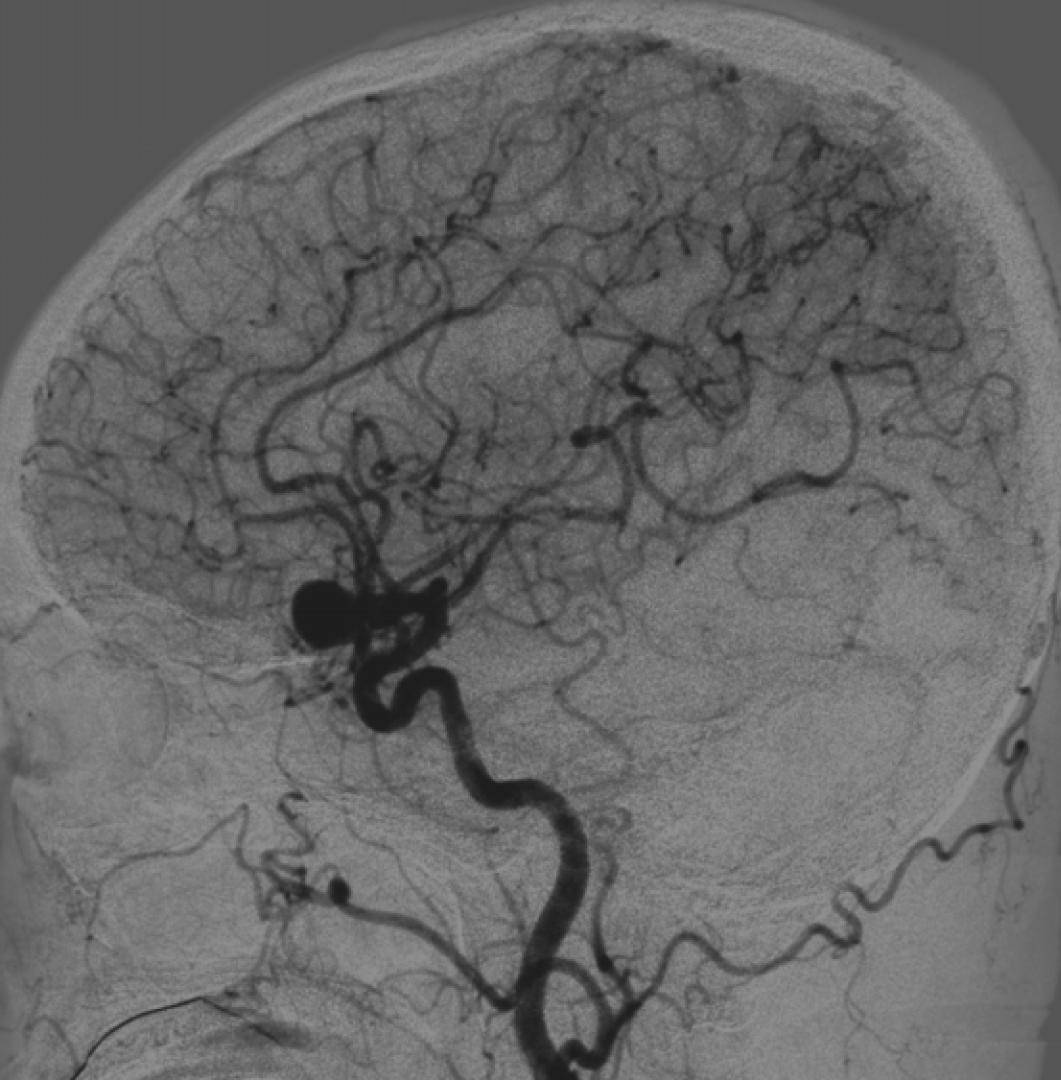

术前侧位DSA

初步诊断:左侧大脑中动脉M1段动脉瘤

侧别、位置:左侧

动脉瘤的形态:囊性

动脉瘤大小:长24.8mm、宽23.1mm、高20mm

动脉瘤颈宽度:6.2mm

载瘤动脉直径:远端3.1mm,近端3.9mm

动脉瘤特征:M1段动脉瘤体积巨大,瘤颈宽大,瘤腔容积大,单纯弹簧圈难以实现致密栓塞,复发风险高。

解剖位置:瘤颈邻近分叉及穿支动脉,M1段血管长度有限,操作空间狭窄,要求支架定位精准且不影响分支灌注。

血管径差:远近端管径不一致,常规FD容易出现贴壁不良或位置不稳。